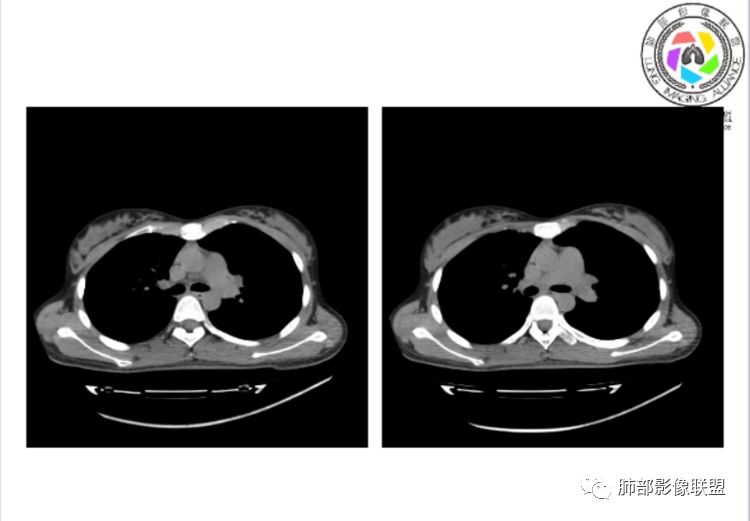

CTPA(CT断层肺血管造影)是对疑似PE患者肺血管系统成像的首选方法,可直观判断肺栓塞的程度和形态,以及累及部位及范围,可以从直接或间接征象进行诊断,但是对亚段及远段肺动脉血栓敏感性较差,联合肺动脉造影可以使PE诊断敏感性增强。

CTPA直接征象:

1、肺动脉中央部分充盈缺损

2、偏心性或附壁充盈缺损

3、骑跨型血栓

4、完全型充盈缺损,动脉截断,远端动脉分支内无造影剂